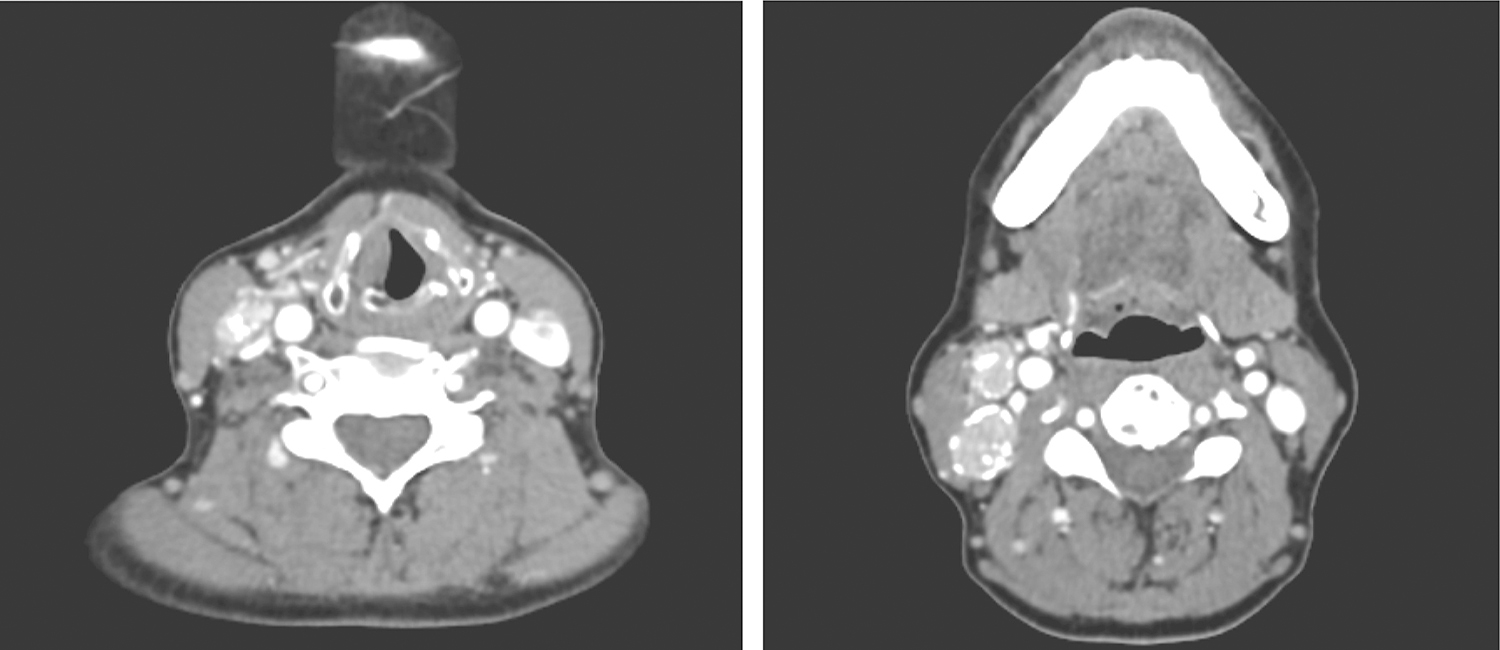

2.2017年8月8日颈胸部增强CT

颈前正中可见一直径1.9cm大小的类圆形低密度影,边界清楚,其内可见一直径0.8cm大小的强化结节影(图3);甲状腺右叶见斑片状低密度影,边界不清楚,其内见斑片状、斑点状钙化密度影;甲状腺左叶见斑片状低密度影;右颈见多发结节状稍高密度影,边缘见环形钙化影,轻度强化(图4)。

图3 颈部增强CT示颈前正中类圆形低密度影内的强化结节影

图4 颈部增强CT示右颈多发结节状稍高密度影伴钙化